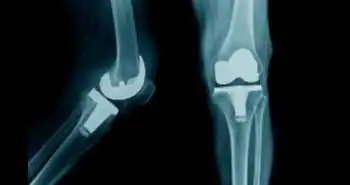

Primary total hip arthroplasty (THA) is a commonly used routine treatment for hip diseases for example osteonecrosis of the femoral head, developmental dysplasia of hips, femoral neck fractures, hip OA, ankylosed hip, etc. As described in this analysis, the approach of posterior capsule repair in total hip arthroplasty had a lower complication rate along with better functional outcomes.

Earlier studies have suggested that posterior capsule repair group offers better clinical outcomes in primary THA. This systematic review and meta-analysis aimed to assess the post-operative outcomes between the 2 procedures i.e. in patients with posterior capsule repair and in those without the posterior capsule repair.

This meta-analysis comprised of 8 comparative studies. A lesser dislocation rate, higher Harris hip score (HHS), and even less post-operative bleeding volume was observed in the posterior capsule repair group as compared to the unrepaired posterior capsule group. No significant difference in range of motion (ROM) was observed.

During primary THA, fixing the posterior capsule during primary THA offers improved functional results, less dislocation rate, and a reduced amount of blood loss.